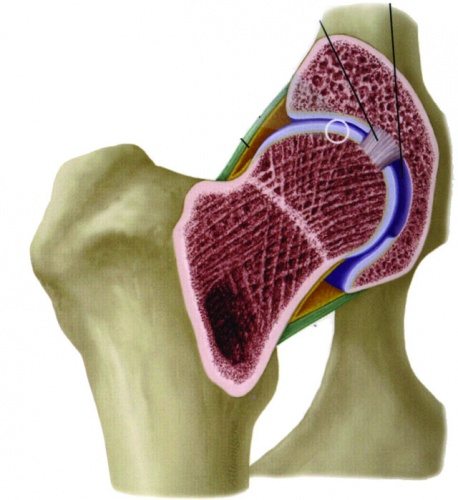

Сустав, расположенный в тазовой области — наиболее крупное соединение в организме человека, берет на себя основную нагрузку. Благодаря внешнему покрытию — эластичному хрящу — существует возможность передвигаться, сидеть, бегать.

Когда происходит зарождение заболевания, нарушается баланс между зарождением новых клеток для восстановления хряща и его разрушением, чаще прогрессирующего характера. У здорового человека хрящ представляет собой эластичное соединение, прочное и позволяющее нормально передвигаться. Под воздействием патологического процесса все описанное выше заменяется тонкой сухой тканью с нарушенной структурой. Как следствие, движения значительно ограничиваются, начинается деформация. Соединительно-тканная оболочка ТБС также преобразовывается на фоне воспалительного процесса и фиброза.

Под действием патологического процесса эластичность хряща стремительно снижается, развивается выраженная симптоматика болезни — утренняя скованность, боли в момент ходьбы и даже сидения.